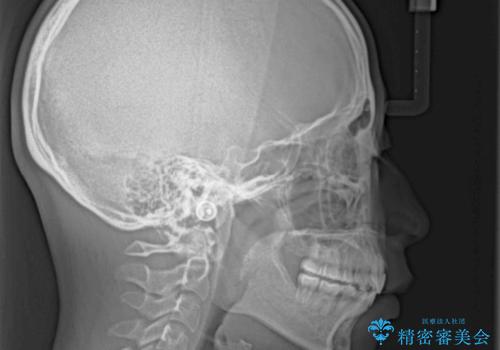

口が閉じられない 抜歯矯正で横顔の印象が劇的に変化

口元の突出感を改善するため、上下左右第一小臼歯4本の抜歯を行い、ワイヤー装置による矯正治療を行うこととしました。

舌の突出癖により上下前歯は非接触であり、非常に前方に飛び出している状態でした。

舌のトレーニングをしっかりと行っていただき、口の閉じやすい歯並びに仕上げることができました。